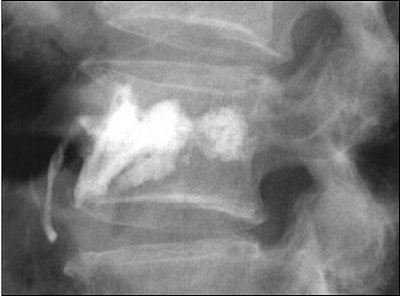

![]() ![]() |

Top, radiography of a compression fracture. Center, vertebroplasty needle insertion. Below, post-procedure. Images courtesy of Dr. Martin Radvany.